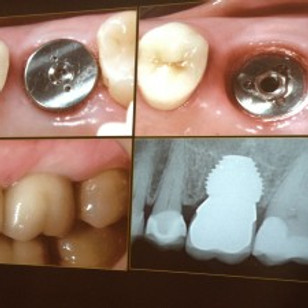

Dental crowns play a central role in many smile makeovers, particularly where teeth are cracked, heavily worn, or discoloured beyond what whitening can address. Our tooth-coloured ceramic crowns are custom-made to blend naturally with your surrounding teeth, restoring both function and aesthetics. Using CEREC technology, some crown treatments can even be completed in a single visit — ideal if you want to refresh your smile with minimal disruption to your routine.

Missing teeth can undermine even the most carefully planned smile makeover. Dental implants are widely regarded as the gold standard for tooth replacement, providing a permanent, natural-looking solution that preserves jaw bone and supports long-term oral health. As part of a full smile makeover, implants can be combined with crowns, veneers, and teeth whitening to deliver a truly seamless result. If you've been putting off addressing a gap in your smile, a combined implant and smile makeover consultation at No 9 is the ideal first step.